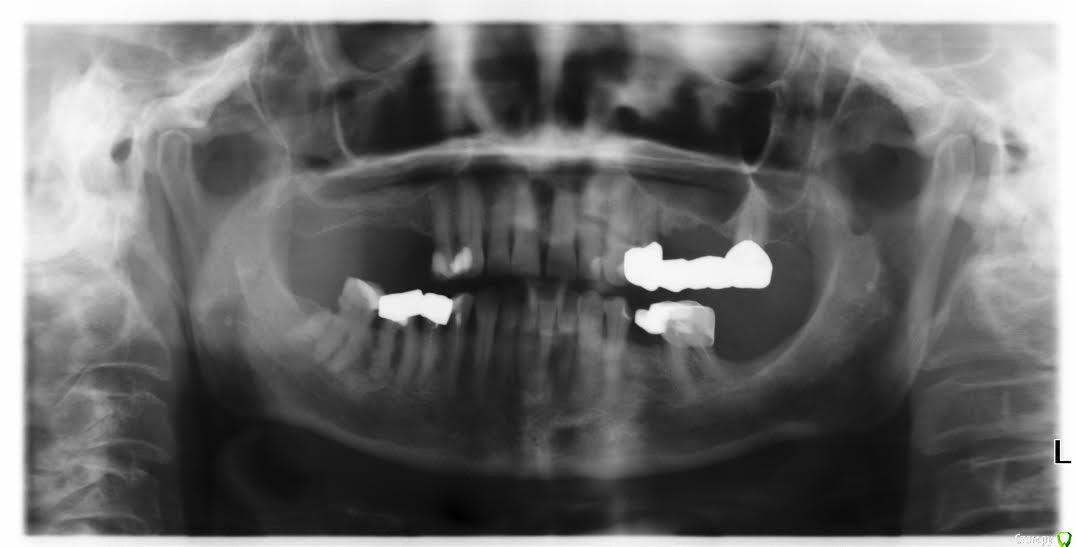

tbk Опубликовано 24 сентября, 2015 Поделиться Опубликовано 24 сентября, 2015 Посмотрите, пожалуйста, реально ли сделать новый мост ( верх, левая сторона) или только съемный протез возможен? Ссылка на комментарий

red_butler Опубликовано 24 сентября, 2015 Поделиться Опубликовано 24 сентября, 2015 Мост не стоит делать, импланты или съемный протез. 1 Ссылка на комментарий

tbk Опубликовано 24 сентября, 2015 Автор Поделиться Опубликовано 24 сентября, 2015 Мост не стоит делать, импланты или съемный протез.спасибо за ответ! а можно ли по снимку сказать хватит ли кости для установки импланта? и возраст пациента 68 лет, диабет, гипертензия, гипотериоз Ссылка на комментарий

red_butler Опубликовано 24 сентября, 2015 Поделиться Опубликовано 24 сентября, 2015 можно ли по снимку сказать хватит ли кости для установки импланта? Нужен синус лифтинг диабет Какого типа? гипертензия, гипотериоз Что с уровнем гормонов и антител? Ссылка на комментарий

tbk Опубликовано 24 сентября, 2015 Автор Поделиться Опубликовано 24 сентября, 2015 Нужен синус лифтинг Какого типа? Что с уровнем гормонов и антител? диабет второго типа, сахар 6-7ттг 2.1 т4-18 Ссылка на комментарий